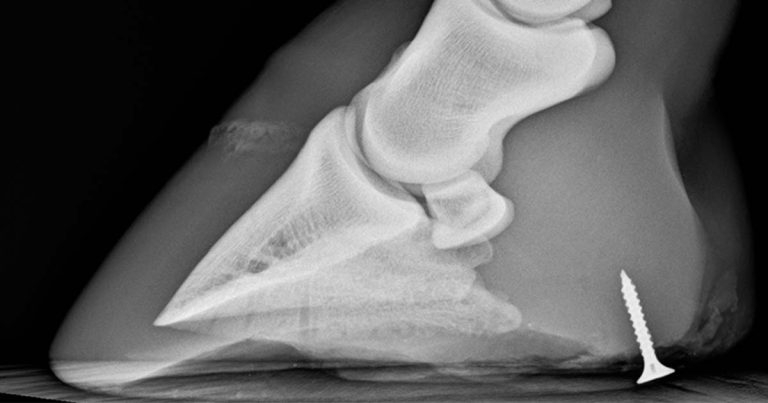

Figure 2. Lateromedial radiograph of the foot of a horse that has stood on a screw. Use of imaging prior to removal gives indication of the orientation and depth of the foreign material.

Evaluation of wounds around a joint, tendon sheath or bursa can be aided with the use of radiography – in particular to assess for the presence of gas that may extend into a synovial structure and foreign material. Where possible, radiographs should be obtained prior to synoviocentesis, thus any presence of gas in a synovial structure should be further investigated (Figure 5).

It is important to remember not all foreign material is radiopaque – objects such as wood can be radiolucent compared to bone and soft tissues.